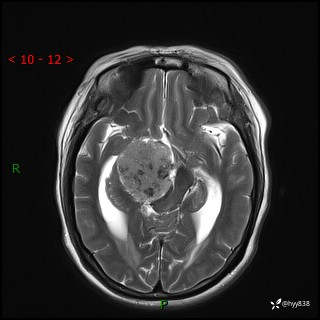

颅脑CT平扫